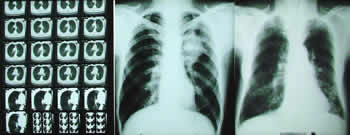

ali i da nas „dovede“ do tačnog mesta poremećaja. Dijagnostika

plućnih bolesti počinje uobičajenim pregledom bolesnika. Može

da obuhvati rendgenski snimak i endoskopiju; međutim, bez

ispitivanja disajne funkcije, naglašava naš sagovornik, nema

kompletne dijagnostike.